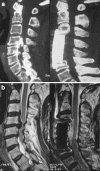

Between May 2002 and October 2006, 19 patients (17 men and 2 women; average age 57.2; range 47-71 years) received anterior corpectomy and fusion for severe ossification of the posterior longitudinal ligament (OPLL) in our department. Preoperative radiological evaluation showed the narrowing by the OPLL exceeded 50% in all cases, and OPLL extended from one to three vertebrae. We followed-up all patients for 12-36 months (mean 18 months). The Japanese Orthopaedic Association (JOA) score before surgery was 9.3 +/- 1.8 (range 5-12) which significantly increased to 14.2 +/- 1.3 (range 11-16) points at the last follow-up (P < 0.01). The improvement rate (IR) of neurological function ranged from 22.2-87.5%, with a mean of 63.2% +/- 15.2%. The operation also provided a significant increase in the cervical lordosis and the cord flatting rate (P < 0.01). No severe neurological complication developed. We therefore concluded that anterior decompression and fusion was effective and safe in the treatment of the selected patients, although OPLL exceeded 50% diameter of the spinal canal.